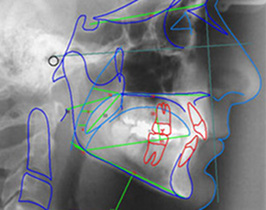

Ortodontia / Aparelhos de Correção Dentária

A Ortodontia é a Especialidade da Medicina Dentaria que estuda o crescimento e desenvolvimento da face bem como o desenvolvimento das funções dos desvios de normalidade, prevenindo, interceptando e corrigindo as más oclusões dentárias. O ortodontista, atualmente inicia o seu tratamento com condutas mais simples, como a manutenção de espaços, nos casos de perda prematura de dentes, corrigindo até os casos mais complexos, como os tratamentos ortodônticos associados com o aumento ou diminuição cirúrgica dos maxilares. A função principal do tratamento ortodôntico é restabelecer a oclusão dentária (perfeito encaixe dos dentes superiores e inferiores), que é fundamental para a correcta mastigação e, consequentemente, adequada nutrição e saúdeoral. Com o restabelecimento da oclusão, evita-se problemas de respiração, deglutição, fala e da articulação facial.

A Oclusão é a especialidade da Medicina Dentária que restabelece a função temporo-mandibular, através do uso de goteiras oclusais e outras técnicas.